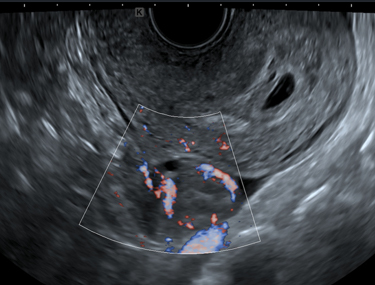

2.血流を検出するシンプルクリアフロー機能の向上で迅速・正確な診断をサポート

Bモード画像※2だけでなく、血流を色付けして表示するカラーフローモードにおいても、送信回路を新たに設計し、送信効率を高めながら送信ビーム形状を最適化することで高精細化を実現しています。血流を高分解能で感度良く描出するシンプルクリアフロー機能は、送受信する信号の時間的なずれや揺らぎを従来よりも抑制してカラー画像におけるノイズを低減し、血流検出性能を向上させたことによって、微細な血流も鮮明に表示します。